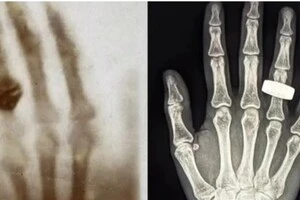

Жінка випадково вистрілила у себе під час чищення пневматичної зброї

На Дніпропетровщині жінка випадково вистрелила собі в голову

Через серйозність травми жінку госпіталізували в лікарню Дніпра з Кам’янського